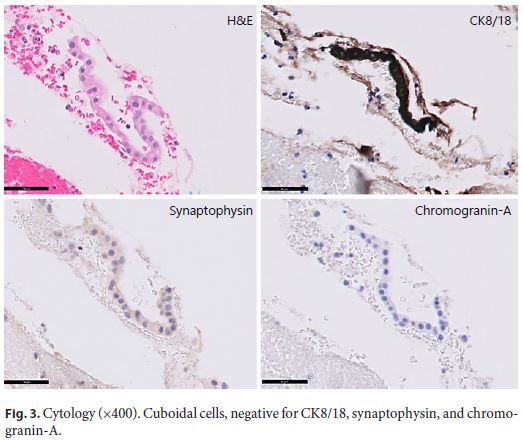

Endoscopic ultrasound (EUS) documented a predominantly microcystic lesion located in the head of the pancreas, measuring 53 × 46 mm, with a few macrocysts and pseudo-solid areas, compressing the CBD and the superior mesenteric vein, and without vascular invasion or Wirsung dilatation (Fig. 2). Fine-needle aspiration of the macrocyst and of a pseudo-solid area was performed. Cyst fluid biochemistry analysis revealed a high amylase level (54,085 UI/L) and a low CEA (2 ng/mL). EUS-fine-needle aspiration cytology showed cuboidal cells, negative for CK8/18, synaptophysin, and chromogranin-A (Fig. 3). For jaundice palliation, endoscopic retrograde cholangiopancreatography (ERCP) was then performed, and a plastic stent was placed. During ERCP, incidental pancreatic duct cannulation and contrast injection occurred, and pancreatography showed a multicystic lesion in the head of the pancreas and confirmed MPD communication (Fig. 4).

At this point, differential diagnosis include sidebranch intraductal papillary mucinous neoplasm, mucinous cystic neoplasm, serous cystic neoplasm and pseudopapillary neoplasm. The previously reported scar, the low CEA, and the presence of cuboid epithelium pointed to a serous cystic neoplasm. Despite the uncertain diagnosis, the presence of high-risk stigmata lead to surgical resection (Whipple procedure), confirming the diagnosis of a serous cystic neoplasm. After the surgery, complete resolution of the symptomatology was noted.

In the reported case, presurgical diagnosis was not straightforward, mainly due to the presence of pseudosolid areas and cystic communication with the MPD with subsequent high amylase, which is a rare feature of serous cystic neoplasm. Although rare, communication with the MPD has been reported occasionally (0–0.6%) in serous cystic neoplasm, requiring a strong suspicion, so that the misdiagnosis of an intraductal papillary mucinous neoplasm is avoided [1].